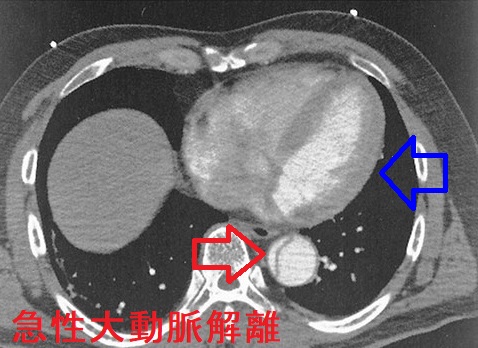

急性大動脈解離とは、大動脈壁の脆弱さ、動脈硬化、高血圧などが原因で、血管内膜に亀裂が入り、中膜が裂け、内腔側が内膜フラップ(intimal flap)になって、その下に偽腔が生じる病態です。

急性大動脈解離では肺血栓塞栓症(肺梗塞)同様、血中Dダイマーが上昇します。